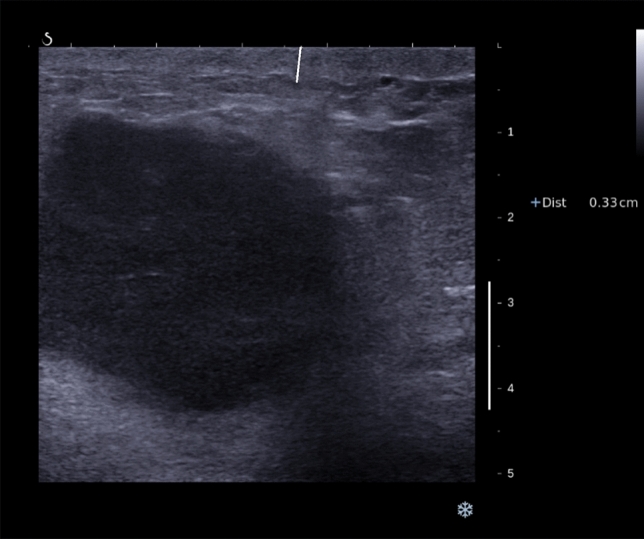

The ultrasound (US) features of breast cancer have recently been shown to have prognostic significance. We aim to assess these features according to molecular subtype. 1140 consecutive US visible invasive breast cancers had US size and mean stiffness by shearwave elastography (SWE) recorded prospectively. Skin thickening (> 2.5 mm) overlying the cancer on US and the presence of posterior echo enhancement were assessed retrospectively while blinded to outcomes. Cancers were classified as luminal, triple negative (TN) or HER2 + ve based on immunohistochemistry and florescent in-situ hybridization. The relationship between US parameters and breast cancer specific survival (BCSS) was ascertained using Kaplan-Meier survival curves and ROC analysis. At median follow-up 6.3 year, there were 117 breast cancer (10%) and 132 non-breast deaths (12%). US size was significantly associated with BCSS all groups (area under the curve (AUC) 0.74 in luminal cancers, 0.64 for TN and 0.65 for HER2 + ve cancers). US skin thickening was associated most strongly with poor prognosis in TN cancers (53% vs. 80% 6 year survival, p = 0.0004). Posterior echo enhancement was associated with a poor BCSS in TN cancers (63% vs. 82% 6 year survival, p = 0.02). Mean stiffness at SWE was prognostic in the luminal and HER2 positive groups (AUC 0.69 and 0.63, respectively). In the subgroup of patients with TN cancers receiving neo-adjuvant chemotherapy posterior enhancement and skin thickening were not associated with response. US skin thickening is a poor prognostic indicator is all 3 subtypes studied, while posterior enhancement was associated with poor outcome in TN cancers.